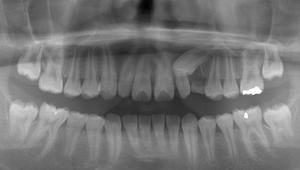

左上3番目の歯がなかなか生えてこないということを主訴に来院された子供さん(13歳)です。 レントゲン写真にて歯の位置を確認しました所、2番目の歯の下に位置しており、かなり方向がずれていることが判明しました。 そこで埋伏歯 […]